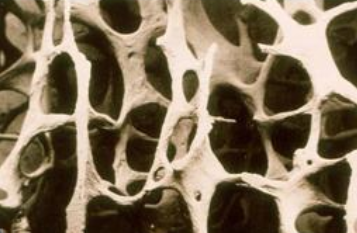

骨质疏松症是一种非常常见的骨骼疾病。 它是一种以骨密度降低、骨微结构破坏、骨痛、骨脆性增加、易骨折为特征的全身退行性疾病。 超声骨密度分析仪厂家骨质疏松症在50岁以上的中老年人群中很常见,尤其是绝经后的女性。 这是因为女性绝经后雌激素分泌减少,导致骨代谢紊乱,骨吸收远远大于骨形成,进而导致骨迅速流失,骨质疏松。

临床上,骨质疏松症的诊断通常基于骨密度(BMD)。 骨密度测试(BMD)可用于包括年轻人在内的所有骨质疏松风险人群,不仅可以诊断骨质疏松,还可以预测骨折的风险,尤其是髋部骨折。骨质疏松症的诊断需要通过骨密度(Bone mineral density, BMD)测量,这是基于BMD检查的t值。 根据骨密度测量结果对骨质疏松程度进行分级。 骨密度测量t值大于-1为正常; 当周期值在-1 ~ -2.5之间时,骨量减少; 当t值小于-2.5时,为骨质疏松; 当t值< -2.5合并脆性骨折时,为严重骨质疏松 。